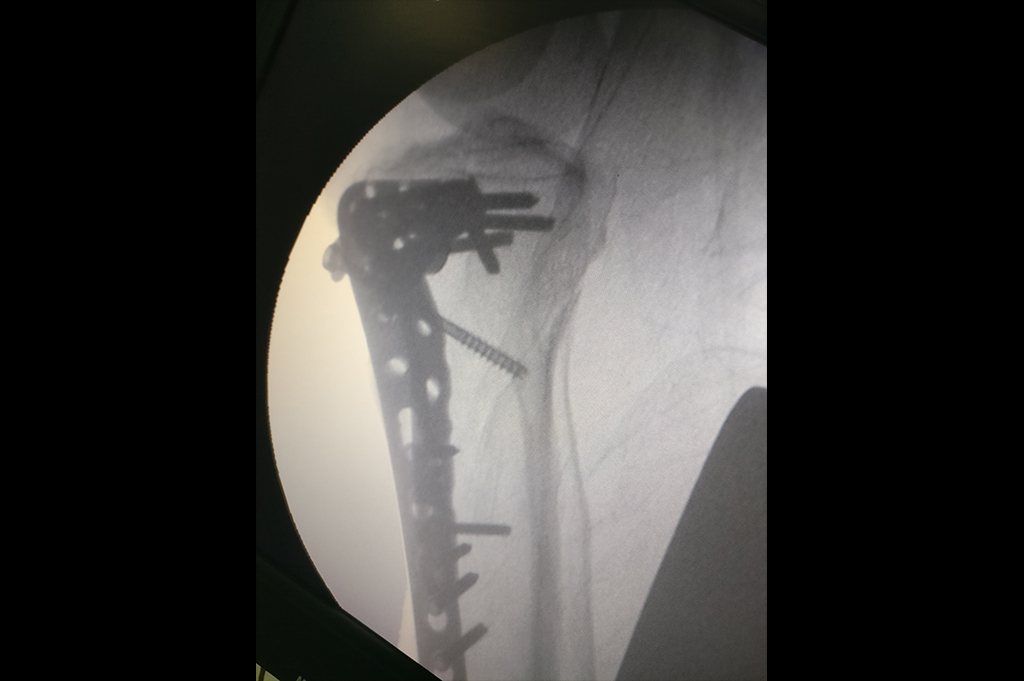

Proximal Humerus